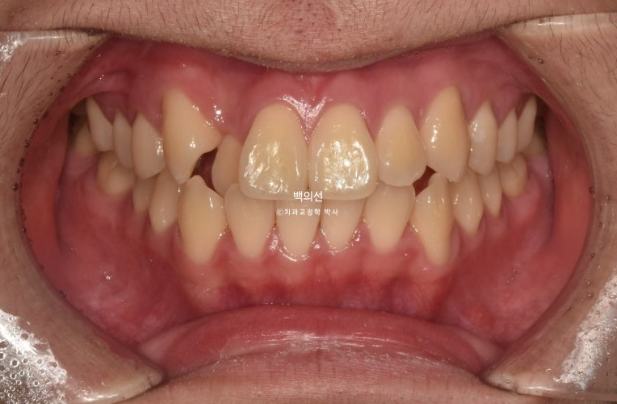

24.04

송곳니 덧니가 있고 덧니 옆 앞니는 입천장으로 나서 아랫니가 거꾸로 물리는 반대교합 입니다.

교합이 뜨는 부분들이 있습니다.

어금니 교합은 좋고 돌출이 없어서 치간삭제 소량 동반한 인비절라인 라이트 권유드렸습니다.

24.12

덧니와 반대교합은 해소가 되었습니다.

교합은 좋고 양쪽 다 1급 교합관계를 보입니다.

배열도 완벽 합니다.